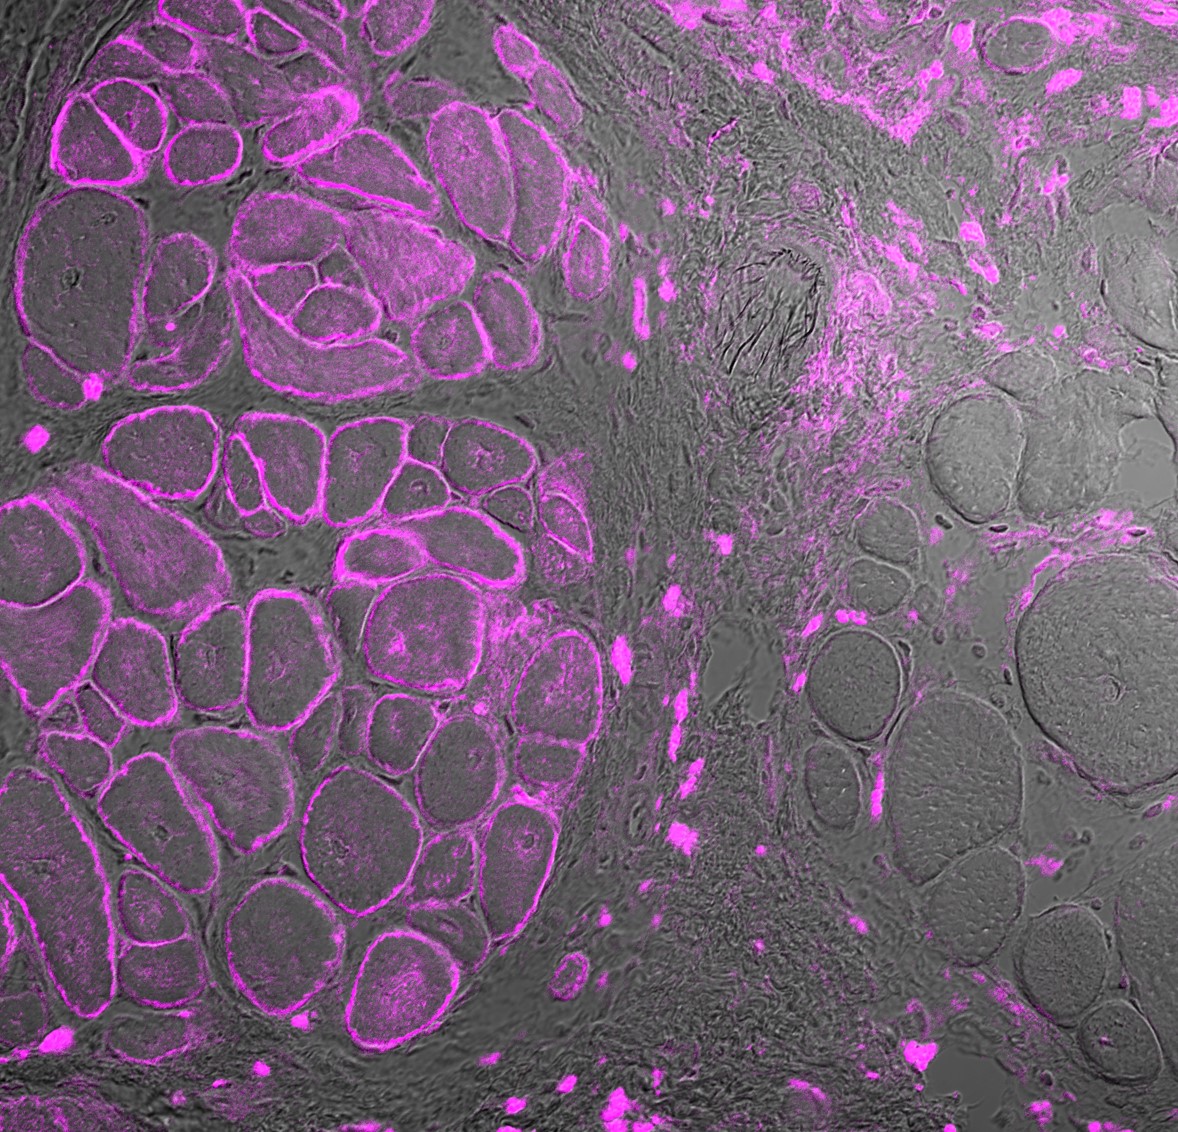

Professorin Simone Spuler und ihre Arbeitsgruppe „Myologie“ am ECRC haben nun unter der Leitung von Dr. Helena Escobar Fernandez Muskelstammzellen von zwei Patient*innen mit Gliedergürtel-Muskeldystrophie entnommen, den genetischen Fehler korrigiert und funktionierende Dysferlin-Proteine in einer Zellkultur produziert. Bei Mäusen verwendeten sie das gleiche Verfahren, um Zellen zu entnehmen, zu bearbeiten und die korrigierten Zellen wieder in Mäuse zu transplantieren. Auch in diesem Modell konnten sie die Proteinfunktion wiederherstellen: Die Muskeln begannen zu wachsen. Das berichten sie in „Nature Communications“.

Um die Dysferlin-Mutation zu reparieren, verwendet Escobar CRISPR-Cas9. Für diese als „Gen-Schere“ bekannte Methode gab es im Jahr 2020 den Nobelpreis. Die molekulare Schere wird zu einer präzise definierten Stelle entlang des DNA-Moleküls geführt und schneidet dort. Dadurch ist die Zelle gezwungen, ihre DNA zu reparieren. Das Ziel ist, dass die krankmachende Mutation während dieses Reparaturprozesses korrigiert wird, sodass das Gen wieder korrekt funktioniert. Die Forschenden testeten ihr Verfahren in mehreren Zellmodellen, mit sehr ähnlichen Ergebnissen: Das Verfahren funktionierte mit einer hohen Erfolgsquote und nur die unbeabsichtigten Folgen waren minimal.

Die Genom-Editierung führte allerdings nicht ganz genau zu der gewünschten Gensequenz – es gab vier Abweichungen im erzeugten Dysferlin-Protein. Diese Veränderungen hat das Team in Zusammenarbeit mit Professor Oliver Daumke, dem Leiter der Arbeitsgruppe „Strukturbiologie Membran-assoziierter Prozesse“ am Max Delbrück Center, gründlich analysiert. „Selbst mit diesen vier Änderungen ist das erzeugte Protein in seiner Funktion dem Wildtyp sehr ähnlich, also der Version, die wir bei gesunden Individuen sehen. Wir haben es entlang beschädigter Zellmembranen nachgewiesen; der Muskel wurde dadurch regeneriert“, sagt Escobar.